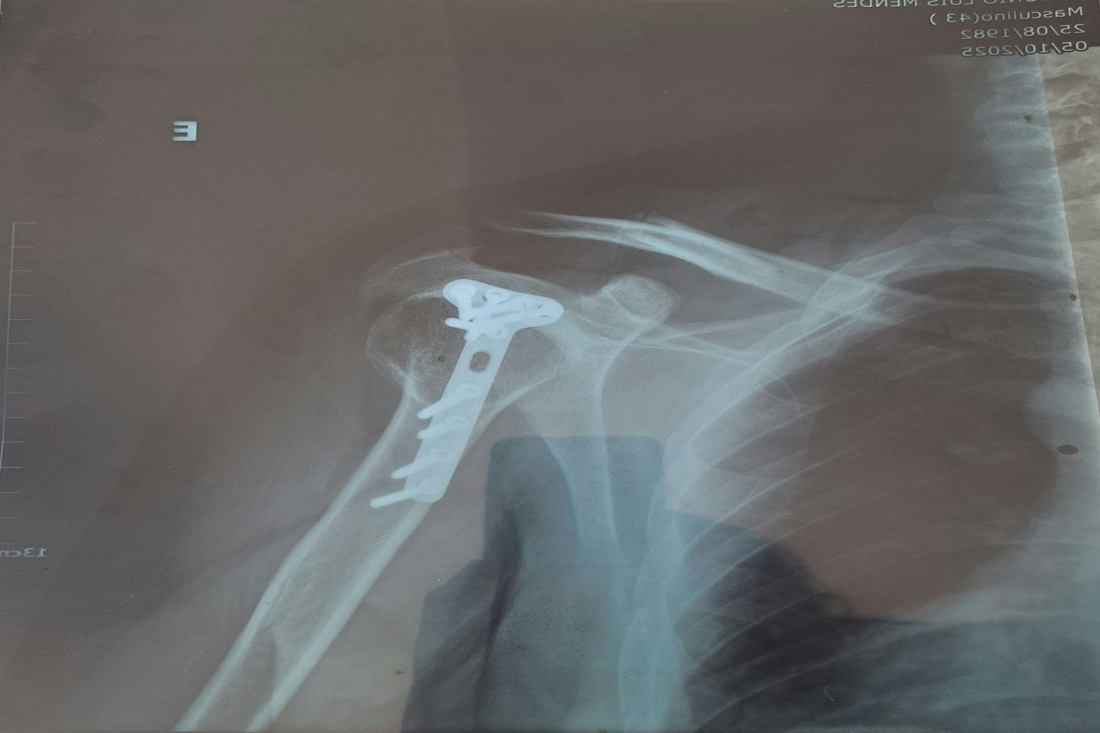

Com o impacto, Tony Lima fraturou a clavícula esquerda e sofreu escoriações pelo corpo. Ambos os motociclistas utilizavam capacete no momento do acidente.

A esposa do jornalista acionou o SAMU, e Tony Lima foi atendido no Hospital Josefina Getirana. Exames apontaram a fratura na clavícula, além de ferimentos no pé e no braço esquerdos. Ele ficará alguns dias em observação, acompanhando a recuperação, para decidir se haverá necessidade de cirurgia futura.

A imagem do metal na radiografia é resultado de outro acidente do radialista